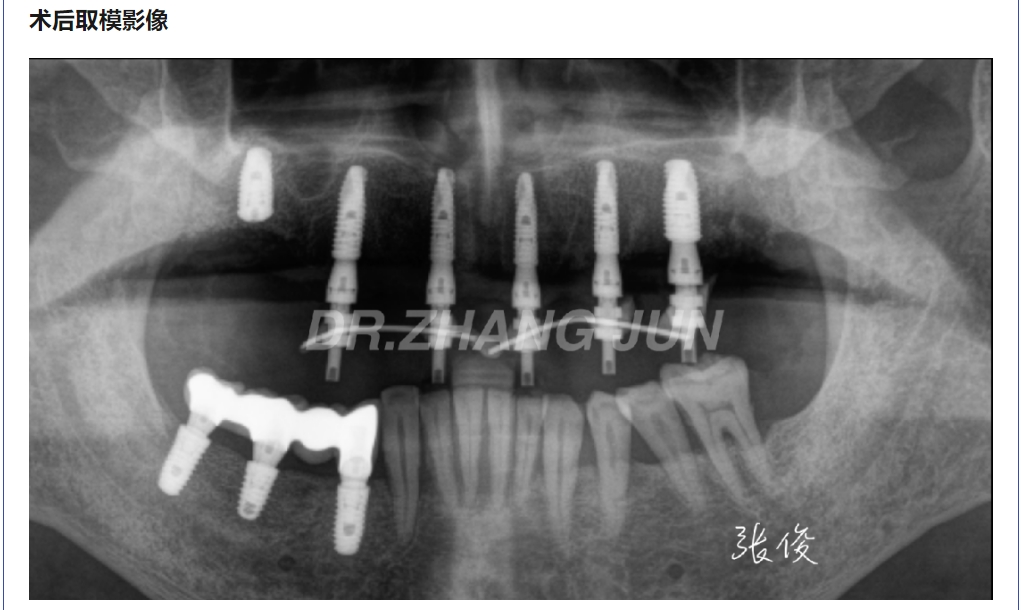

病例分享 | 半口即刻负重一例